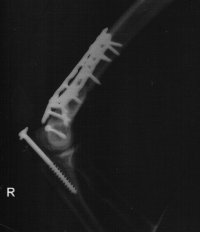

This is my right elbow after surgery....

Post op.jpeg